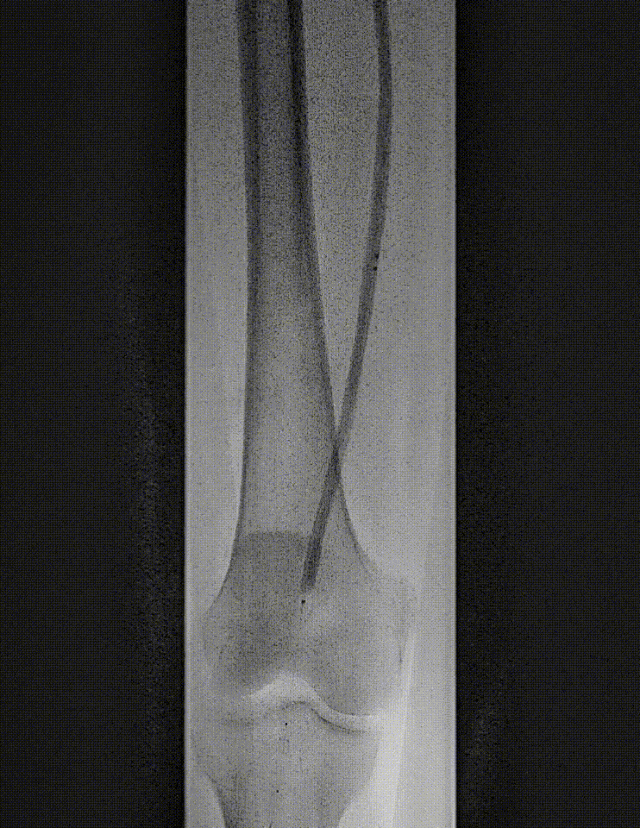

图:造影及通过病变

图:IVUS确认

图:Jetstream 应用

图:DCB 5-250 扩张及全程造影